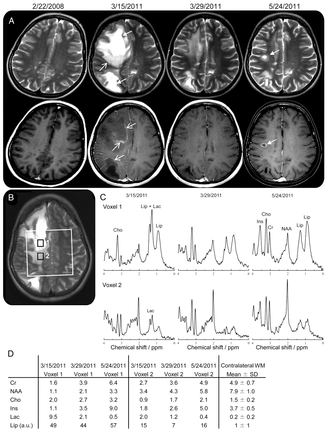

头颅MRI显示2大在右半脑白质病变周围vasogenic水肿、质量效应,和开环后增强钆管理局(图块状脱髓鞘簇状)。这一建议多焦点的,这是由核磁共振光谱(图罪犯)。化脓性脓肿不太可能,因为没有扩散的限制。

(A)轴向T2(上面一行)和gadolinium-enhanced t1加权磁共振成像(底下一行)说明损伤演化在基线(2008年2月22日),在录取的时候我们医院(2011年3月15日),和随访期间(2011年3月29日,2011年5月24日)。2011年3月15日,病人出现块状病变簇状多焦点的两个半球特别是右边。病变的一部分在t2加权像上显示坏死和囊性外观(关闭头箭头)和其他部分显示出积极的迹象脱髓鞘与血脑屏障的破坏导致对比度增强(打开头箭头)。immune-modulating治疗停止后,脱髓鞘区域的体积减少,暗示remyelination,对比度增强消失(2011年3月29日,看到MRI)。然而,在后续新多发性硬化病变活动性炎症的对比度增强发生(封闭的头部MRI的箭头5月24日,2011)。(B)定量化学位移成像(CSI)进行新闻本地化(重复时间/回波时间3000/30毫秒),与巨大的白色表示感兴趣的体积。(C)上面一行:纵向光谱从体素1在囊性/坏死区。最初的光谱(2011年3月15日)显示了一个几乎没有完整的所有代谢产物除了choline-containing化合物(Cho)由于膜退化。它也显示了一个巨大的海拔乳酸(Lac)由于炎症组件,和脂质(唇)符合巨噬细胞的存在。随着时间的推移(2011年3月29日,5月24日,2011),NAA略有改善,但仍低,由于neuro-axonal损失或损害,而肌酸(Cr)、肌醇(Ins),由于神经胶质增生和曹强烈增加。 Lac has diminished, but Lip remains very prominent. Bottom row: longitudinal spectra from the surrounding border (voxel 2) are initially characterized by a reduced concentration of all metabolites, probably due to the diluting effect of edema, and the presence of Lac. Over time, the spectra almost normalize, although NAA remains slightly reduced and some lipid signals remain visible. (D) Metabolite concentrations (in mmol/L) corresponding to these spectra were quantified with LCModel, and compared to concentrations in contralateral white matter (WM).